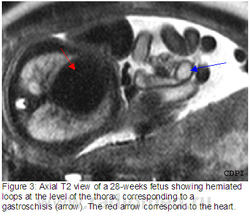

Данное врожденное заболевание характеризуется двумя основными дефектами: эктопией сердца и дефектом передней брюшной стенки (чаще всего наблюдается омфалоцеле, но может встречаться и гастрошизис) в сочетании с нарушением развития трех, связанных между собою структур: дистального отдела грудины, передней части диафрагмы и диафрагмального отдела перикарда. Имеются сообщения о вариантах классической формы, которые характеризуются неполным проявлением данного синдрома.

Диагностика. Наличие полной формы дизрупции порока развития передних стенок грудной клетки и брюшной полости, которая сопровождается пятью признаками, описанными J.R. Cantrell et al., является классической формой пентады и может быть выявлена при ультразвуковом исследовании начиная с середины второго триместра. Обнаружение сокращающегося вне пределов грудной клетки сердца в сочетании с омфалоцеле позволяет установить диагноз пентады. Для исключения хромосомных аномалий рекомендуется проведение кариотипирования. Вследствие компрессии органов как грудной клетки, так и брюшной полости могут возникать асцит и гидроторакс.

Патогенез. Остановка развития сегмента латеральной мезенхимы в период от 14-го до 18-го дня после зачатия приводит к незакрытию брюшной стенки и неполному слиянию наружных первичных тяжей.